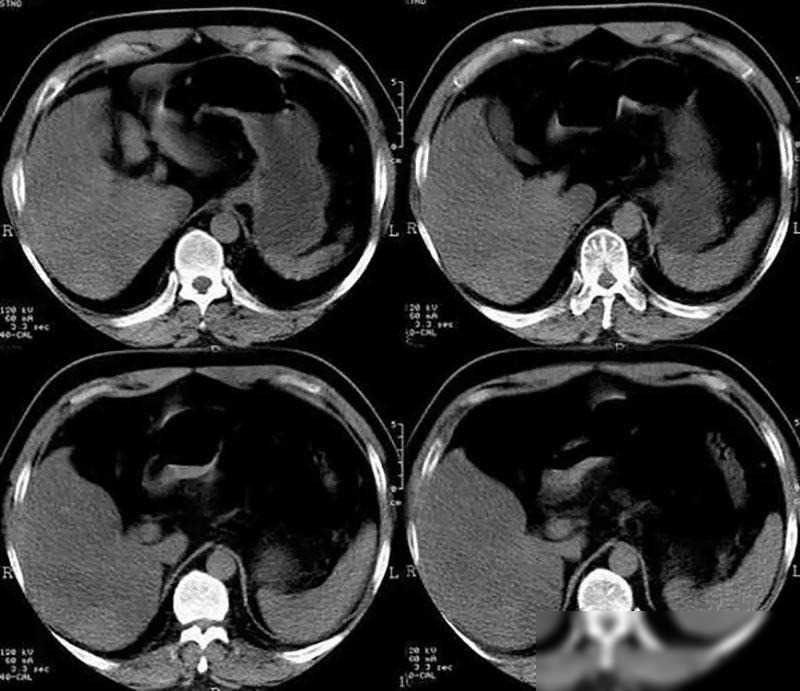

生活方式的奇迹:在拥有坚定意志和积极生活态度的支持下,凌志军的身体在检查中展现出奇迹。五年后的他,癌细胞全部消失,身体各项指标回归正常。这不仅是医学奇迹,更是生活态度的奇迹。